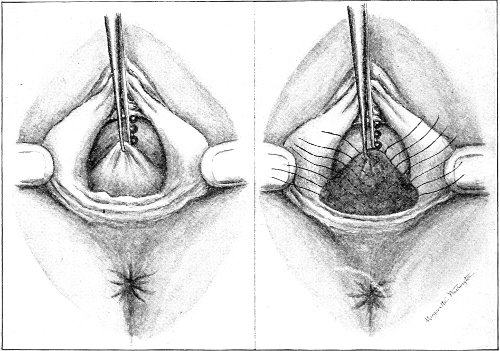

The secondary operation is performed at any time after cicatrization has occurred—often many years after the receipt of the injury. This operation is at present one of the commonest in gynecology, because the injury is not detected, is neglected, or is improperly repaired after labor. In the secondary operation an anesthetic is necessary. The mucous membrane must be removed or denuded on the posterior wall and about the mouth of the vagina, in order that the lacerated structures may be brought again in apposition. The denudation is best made by means of scissors curved on the flat (Figs. 24 and 25).

The strip of mucous membrane to be removed is picked up with a tenaculum (Fig. 26) or with tissue forceps 65 (Fig. 27); the scissors are placed with the blades parallel to the surface to be denuded, and the strip is cut away evenly, in one piece if possible. A similar contiguous strip is removed, and so on until the necessary surface is bare. Sponges in holders (Fig. 28) or continuous irrigation may be used to remove blood.

For all operations on the perineum round-pointed needles curved at the tip should be used (Fig. 29). The tissues are always sufficiently soft for the passage of such a needle. A needle with a cutting edge is unnecessary and may increase the bleeding.

The needle may be held in any kind of needle-holder preferred. The Emmet needle-holder (Fig. 30) is very convenient.

The point of the needle should be guided and held by the tenaculum. The tenaculum must always be held in a plane parallel with the plane of the needle-holder; otherwise the needle-point may escape from the embrace of the tenaculum. 66

Silver wire and silkworm gut are the best sutures in the operation of perineorrhaphy.

The suture is conveniently attached to the needle by means of a silk carrier (Fig. 31).

The sutures may be fastened by passing the ends through a perforated shot which is slipped down to the line of union and compressed by the shot-compressor (Fig. 32). All blood should be carefully removed from the surfaces that are brought together. The sutures should only be sufficiently tense to produce accurate apposition. A light gauze drain should be introduced in the vagina, and should be removed in forty-eight hours. Afterward one vaginal douche of about a quart of warm bichloride solution (1:2000) should be administered every day. After the douche the labia should be separated and the vagina carefully dried by cotton held in dressing-forceps. Except in those cases in which the sphincter ani is involved, the bowels may be moved on the second or third day. The woman should stay in bed for two weeks, at the end of which time the sutures should be removed. 67 She should avoid heavy lifting, long standing, and bicycle- or horseback-riding for two months after the operation. Constipation should always be avoided. Coitus may be resumed six weeks after operation.

Slight Median laceration of the Perineum.—In this injury the tear takes place through the fourchette. Posteriorly it may extend as far as the sphincter ani muscle. Upward it may extend for an inch up the posterior vaginal wall. The appearance of this tear is shown in Fig. 33. It will be noted that, as this tear takes place in the median line, none of the muscles that support the perineum are involved, nor are the planes of fascia injured. The perineum is slightly split, and the insertions and origins of the muscles and the fascia are slightly separated. The supporting structures of the perineum and the pelvic floor are, however, uninjured.

Fig. 33.—Recent slight median laceration of the perineum: sutures introduced.

If this tear is detected after labor, it should be closed by the immediate operation. A slight tear involving chiefly the cutaneous aspect of the perineum should be closed by three or four sutures introduced from the outside, as in Fig. 33. The needle should be introduced about a quarter of an inch from the edge of the wound. It should not be passed parallel with the plane of the lacerated surface, but should be swept outward and then inward toward the 68 angle at the bottom of the tear (Fig. 34). It may either emerge at the angle and be re-introduced, or it may be passed directly through to the skin-margin on the opposite side of the wound. If the suture is passed in this way, there will be perfect apposition throughout the whole surface of laceration. If the sutures are improperly passed, there may result only apposition of the skin-edges.

Fig. 34.—Diagram representing the correct and the incorrect method of passing the suture for closure of slight perineal laceration.

If the laceration extends up the posterior vaginal wall, two sets of sutures must be introduced—one on the vaginal aspect of the tear, and one on the skin aspect (Fig. 35).